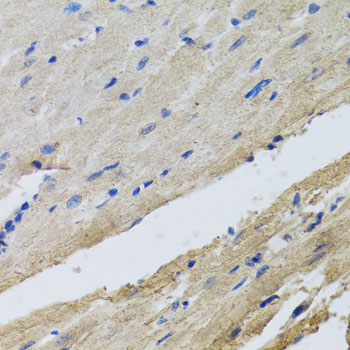

Immunohistochemistry of paraffin-embedded rat heart using FECH at dilution of 1:100 (40x lens).